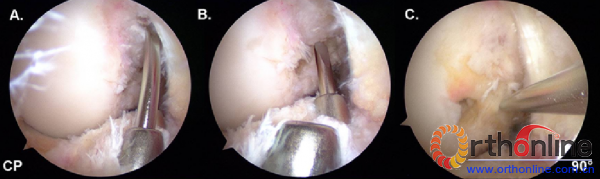

图7:右膝关节屈曲90度,中间入路观察的关节镜示图。该图比较了三种钻取AM股骨隧道的方式:A、经AM胫骨隧道钻取;B、经PL胫骨隧道钻取;3、经前内辅助切口钻取。通过比较,只有经前内辅助切口才能使导针到达AM股骨解剖位置。